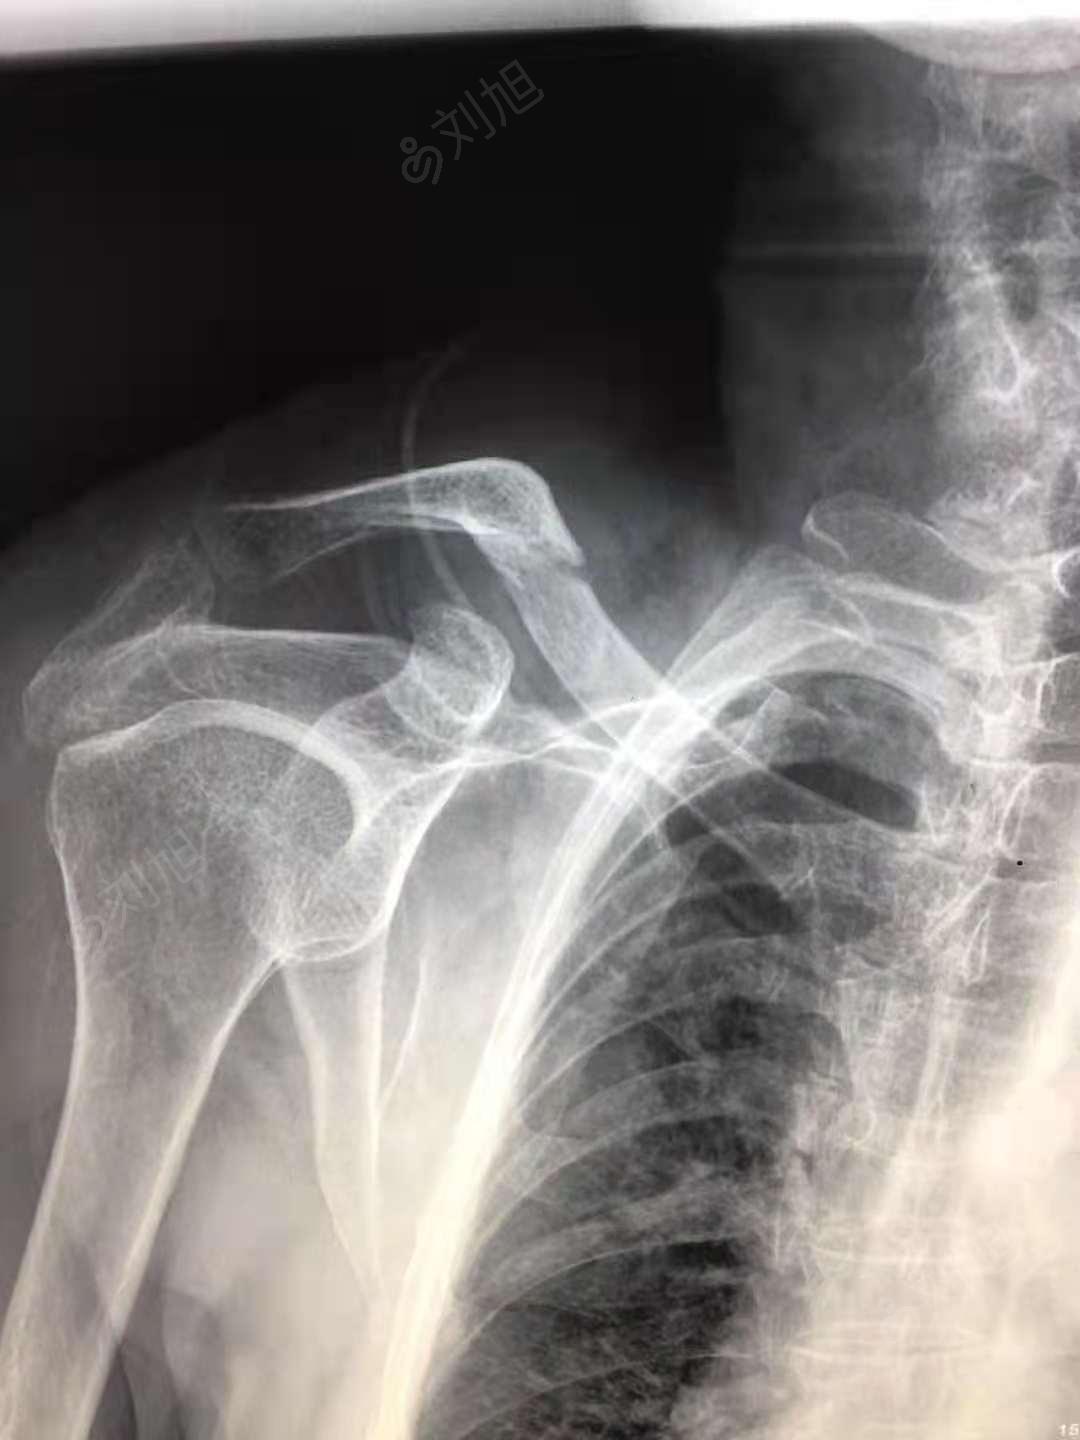

右侧锁骨骨折